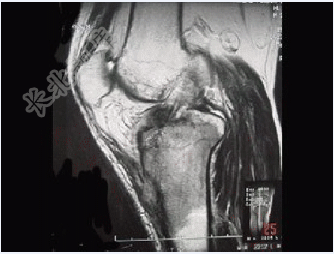

- 单项选择题患者女,28岁,右膝跌伤伴疼痛9年,加重及活动障碍1年半,经药物治疗及理疗后病情无好转,既往无特殊病史,查体跛行步态,触痛,请结合所提供的图像,选择最佳选项( )

A、骨巨细胞瘤

B、结核

C、骨肉瘤

D、滑膜肉瘤

E、软骨肉瘤